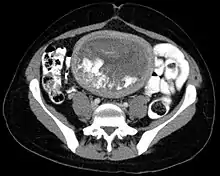

The diagnosis is strongly suggested by ultrasound (sonogram), but definitive diagnosis requires histopathological examination. On ultrasound, the mole resembles a bunch of grapes ("cluster of grapes" or "honeycombed uterus" or "snow-storm").[14] There is increased trophoblast proliferation and enlarging of the chorionic villi, and angiogenesis in the trophoblasts is impaired.[15]

In 10 to 15% of cases, hydatidiform moles may develop into invasive moles. This condition is named persistent trophoblastic disease (PTD). The moles may intrude so far into the uterine wall that hemorrhage or other complications develop. It is for this reason that a post-operative full abdominal and chest X-ray will often be requested.